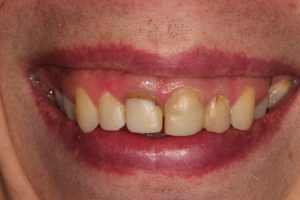

Trauma to Upper Front Teeth

Both central incisors were broken, leaving just the roots. Unfortunately, there wasn’t enough tooth to repair these teeth and they were subsequently removed. Dental implants were placed to restore the missing teeth.